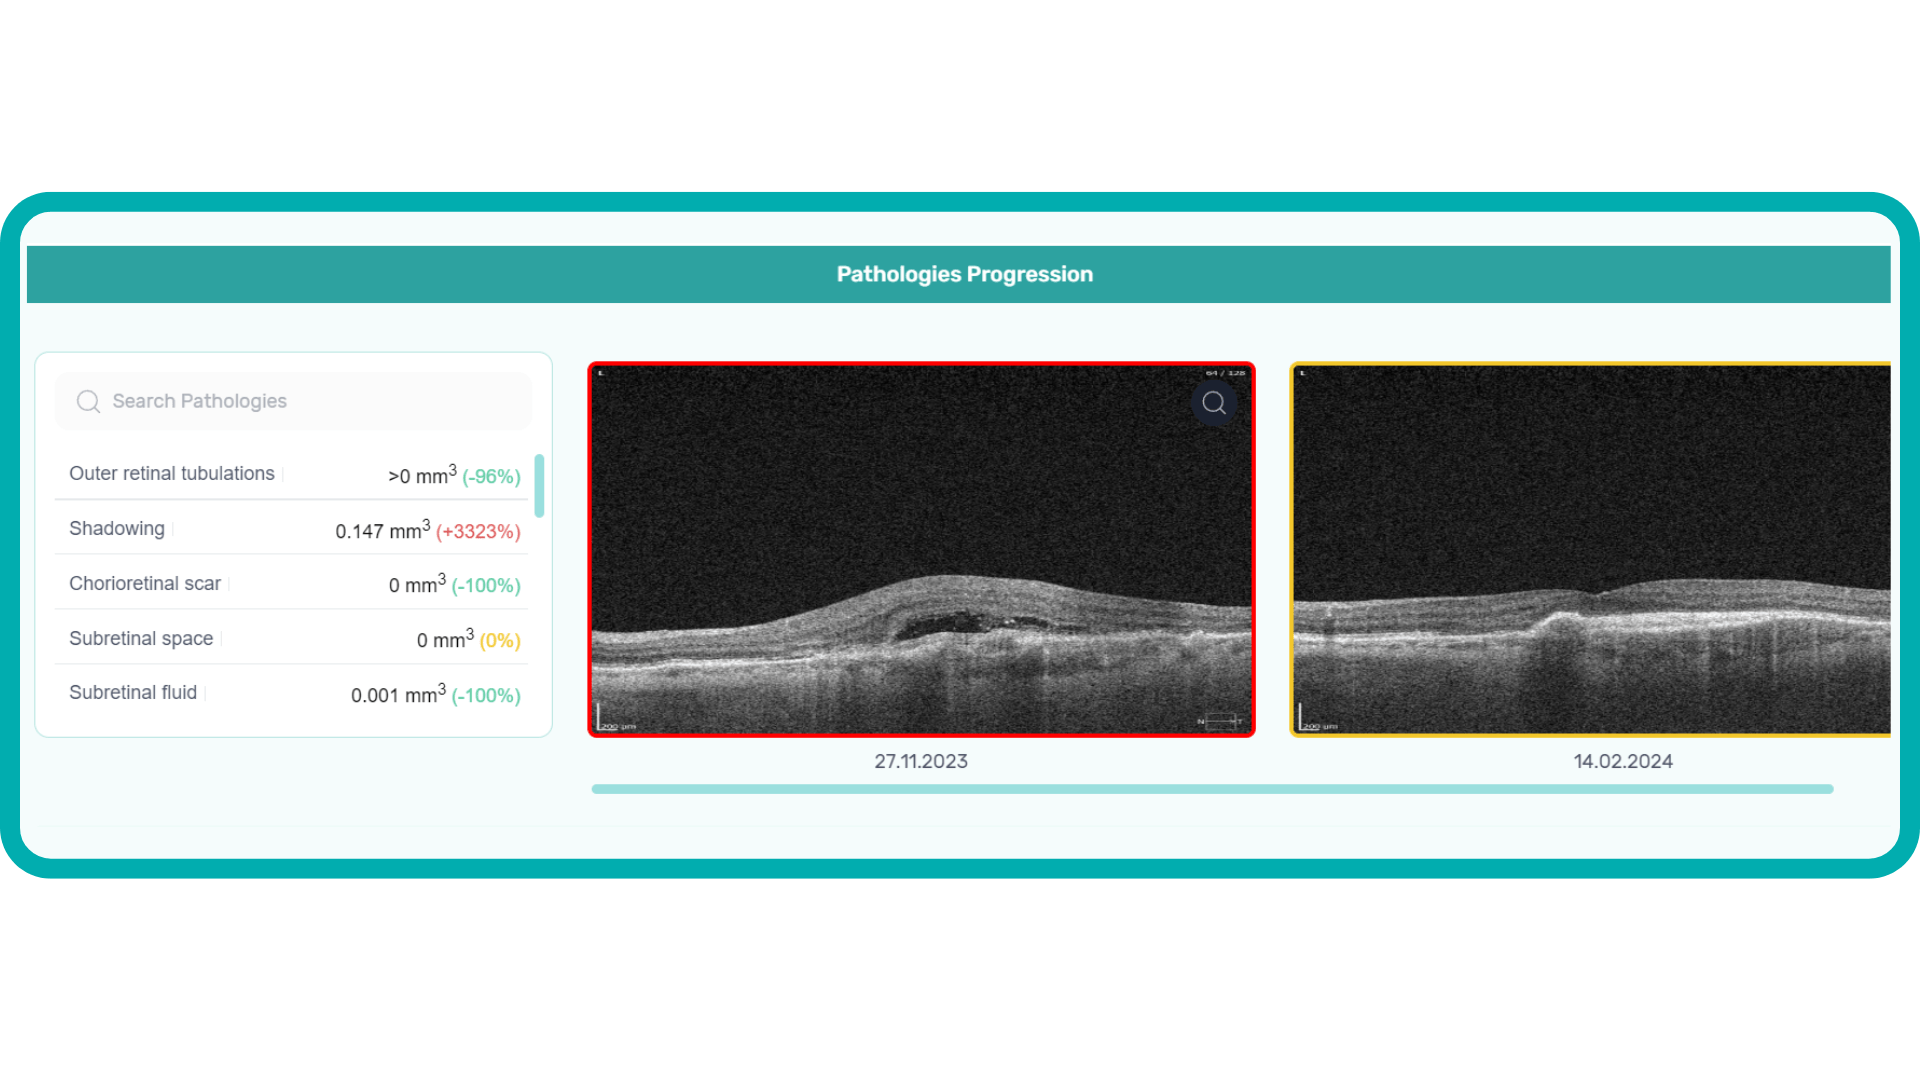

AI-assisted readings of OCT scans are already helping not only with pathology detection but also with the analysis of its progression or response to treatment. This represents a new approach to monitoring, where practitioners no longer need to sift through various patient notes but can directly compare reports from previous examinations and observe how, for instance, shadowing has changed in micrometers.

Measuring treatment progress: biomarkers tracking, pathology progression

Imaging biomarkers are a particularly attractive option for clinical practice due to their non-invasive and real-time nature. Quantitative measurements of retinal thickness, fluid volume, and other biomarkers relevant to diseases like diabetic retinopathy and age-related macular degeneration aid in treatment monitoring.

OCT reports with customized measurements and selected biomarkers, retinal layers, or segments allow for precise focus on treatment monitoring and patient response to therapy. This personalized approach enhances clinical decision-making by highlighting each case’s most relevant information.

In current clinical practice, macular damage assessment typically involves measuring the distance between the ILM and RPE layers, summarized in a post-scan report.

However, these reports often fall short of visualization best practices, employing ineffective or inconsistent color schemes. Additionally, they lack flexibility, with static visuals preventing in-depth examination of specific details. Despite these limitations, these reports remain valuable for many clinicians by distilling complex data into a manageable format.

Enhanced OCT data visualization offers a promising solution to these challenges. It enhances report clarity and comprehensibility while preserving the richness of the underlying data.

Let’s explore how this applies to a clinical case, such as monitoring a patient with Wet AMD during follow-up visits.

Data demonstrates that OCT findings can reveal the onset or progression of neovascular AMD before a patient reports new symptoms or changes in visual acuity. In fact, OCT images are reported to have the best diagnostic accuracy in monitoring nAMD disease states. This underscores the importance of key OCT findings or biomarkers in personalizing anti-VEGF treatment, achieving disease control, and reducing monitoring burdens.

Central Retinal Thickness emerged as one of the earliest OCT biomarkers used as an outcome measure in clinical trials for nAMD.

However, due to confounding factors, CRT’s use in outcome-based assessments of nAMD varies. Thus, it is essential to evaluate additional morphological changes alongside retinal thickness and their relationships with functional outcomes.

It has been reported that OCT images have the best diagnostic accuracy in monitoring nAMD disease states.

Another finding that is correlated with a worsening VA due to the associated photoreceptor defects is any damage to the four outer retina layers, including the RPE, interdigitation zone (IZ), ellipsoid zone (EZ), and external limiting membrane band (ELM).

OCT is a valuable imaging tool for visualizing subretinal hyperreflective material (SHRM). It can automatically identify and quantify SHRM and fluid and pigment epithelial detachment to calculate the overall risk of worsening visual outcomes associated with SHRM.

Subsequent follow-up visits will then display the most relevant picture, highlighting the most pertinent biomarkers for tracking a particular pathology (wet AMD in our example) and comparing their volume, progression, or regression through visits.

Another helpful option is retinal layer segmentation, which focuses solely on the retinal layers of interest for the specific case.

This level of customization empowers clinicians with a comprehensive yet targeted view of the patient’s condition. It saves time from manually detecting anomalies on scans and facilitates informed decision-making and personalized treatment plans.